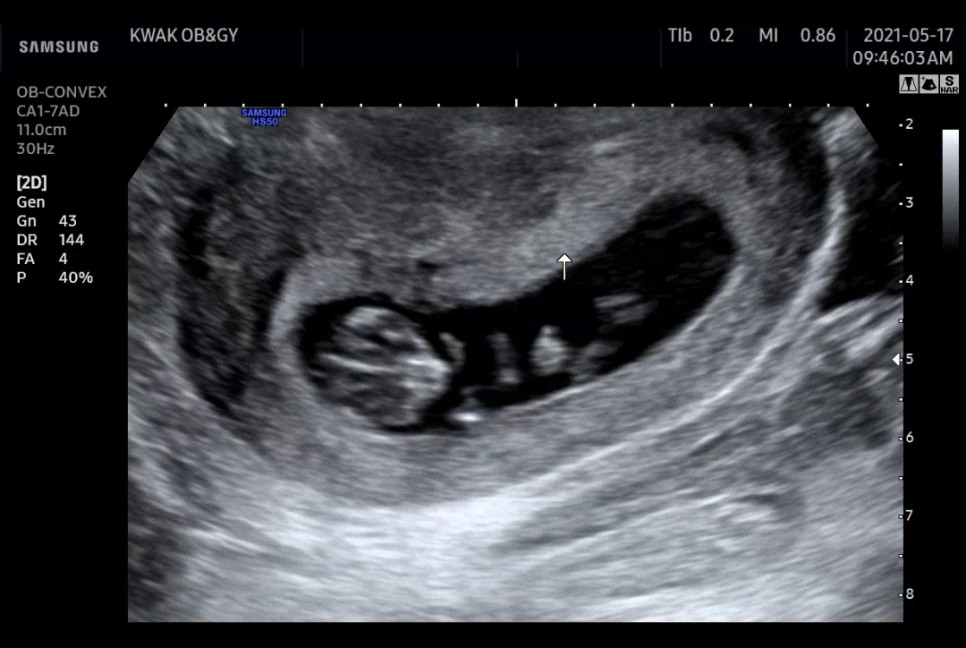

젤리곰 초음파 10w

2주 동안 많이 자란 홍창!아기의 태명을 ‘똑똑’으로 지어주었습니다.

요즘 배 토실토실 하면서 아기랑 만나는 시간이 행복해요입덧은 힘들지만 아기는 귀여워…♡

딱 이 시기에 밖에 볼 수 없는 초음파제는 대충 머리, 가슴, 배, 다리로 나뉘는 것이 보입니다. (신기)

초음파로 똑똑이 보러 갈 날이 기다려지는 임신 초기에요.